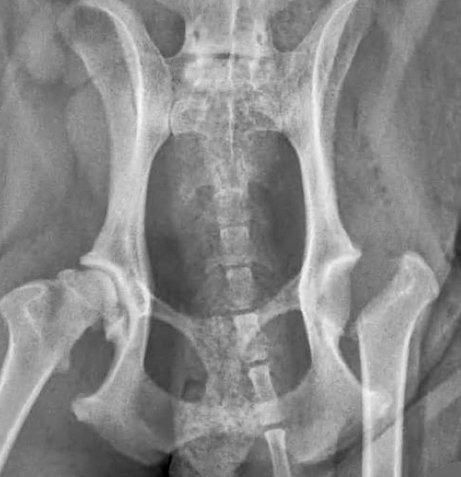

2.2.2 Beckenschwenkosteotomien (TPO/DPO)

Bei den 2- bzw. 3-fachen Beckenschwenkosteotomien werden Knochenschnitte an bestimmten Stellen des Beckens ausgeführt, um die Beckenpfanne mithilfe einer speziellen Knochenplatte und Schrauben seitlich neu auszurichten und damit eine reduzierte Laxizität, verbesserte Kongruenz und Reduktion der fokalen Überlastung zu erzielen. Der Eingriff ist nicht bei allen Patienten möglich/effektiv und wird im Regelfall nur innerhalb des ersten Lebensjahres durchgeführt.